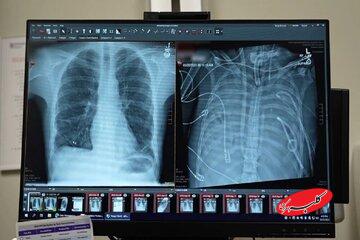

یک مرد ۳۳ ساله بعد از اینکه گروه پزشکی، اعضای بدنش را با یک سیستم ریه مصنوعی خارجی جایگزین کردند که توسعه یافته بود تا او را زنده نگه دارند که بتواند پیوند دو ریه دریافت کند، به مدت ۴۸ ساعت بدون ریه‌هایش زنده ماند.

قبل از قرار گرفتن روی سیستم ریه مصنوعی، این مرد دچار سندرم حاد دیسترس تنفسی شده بود که یک وضعیت اغلب تهدیدکننده حیات است که در آن ریه‌ها نمی‌توانند اکسیژن کافی جذب کنند و این مشکل توسط ویروس آنفلوانزا ایجاد شده بود. سپس او روی ونتیلاتور قرار گرفت، اما دچار عفونت مقاوم به دارو شد. این عفونت باعث شد قسمت‌هایی از ریه‌های او پر از چرک شود و او وارد شوک سپتیک شود که در این مرحله قلب و کلیه‌هایش شروع به از کار افتادن کردند.

بهارات می‌گوید: او خیلی بیمار بود، دچار ایست قلبی شد و در حال مرگ بود. از آنجا که این مرد خیلی بیمار بود که پیوند ریه دریافت کند، گروه پزشکان تصمیم گرفتند ریه‌های او را که منبع عفونت بود، بردارند.

به طور شگفت‌انگیز، مرد شروع به بهبود سریع کرد. در عرض ۴۸ ساعت، او همه داروها برای حمایت از فشار خون را کنار گذاشت، عملکرد کلیه او کاملا بازیابی شد و قلب او به طور طبیعی کار می‌کرد. در این مرحله، مرد پیوند دو ریه را دریافت کرد و سال‌ها بعد هیچ نشانه‌ای از رد عضو یا اختلال عملکرد ریه نشان نداد. اکنون تقریبا سه سال از انجام این کار گذشته است و حال بیمار واقعا خوب است.